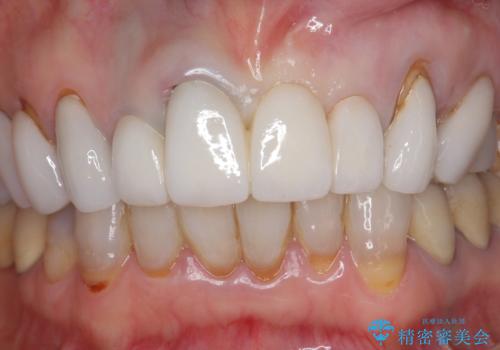

[ セラミック治療 ] 歯ぐきの際の黒ずみを改善したい

クラウンマージンの再設定を行うことで、黒ずんだ部分を再度覆い、審美障害を改善します。

- 52.8万円(ジルコニアクラウン×4・仮歯×4)費用は治療当時の料金となります